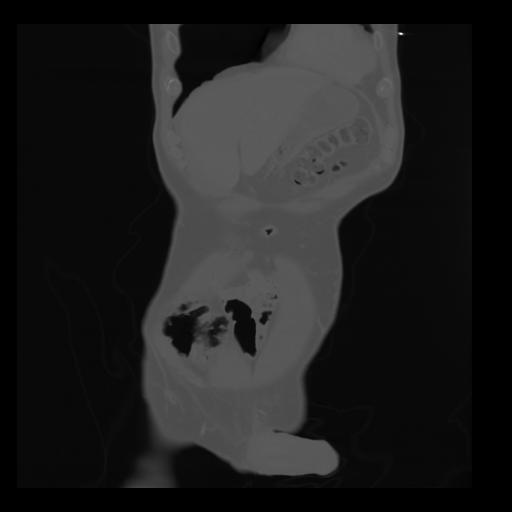

35 CUERPO,CE,Coronal,3.000,CUERPO,Coronal,